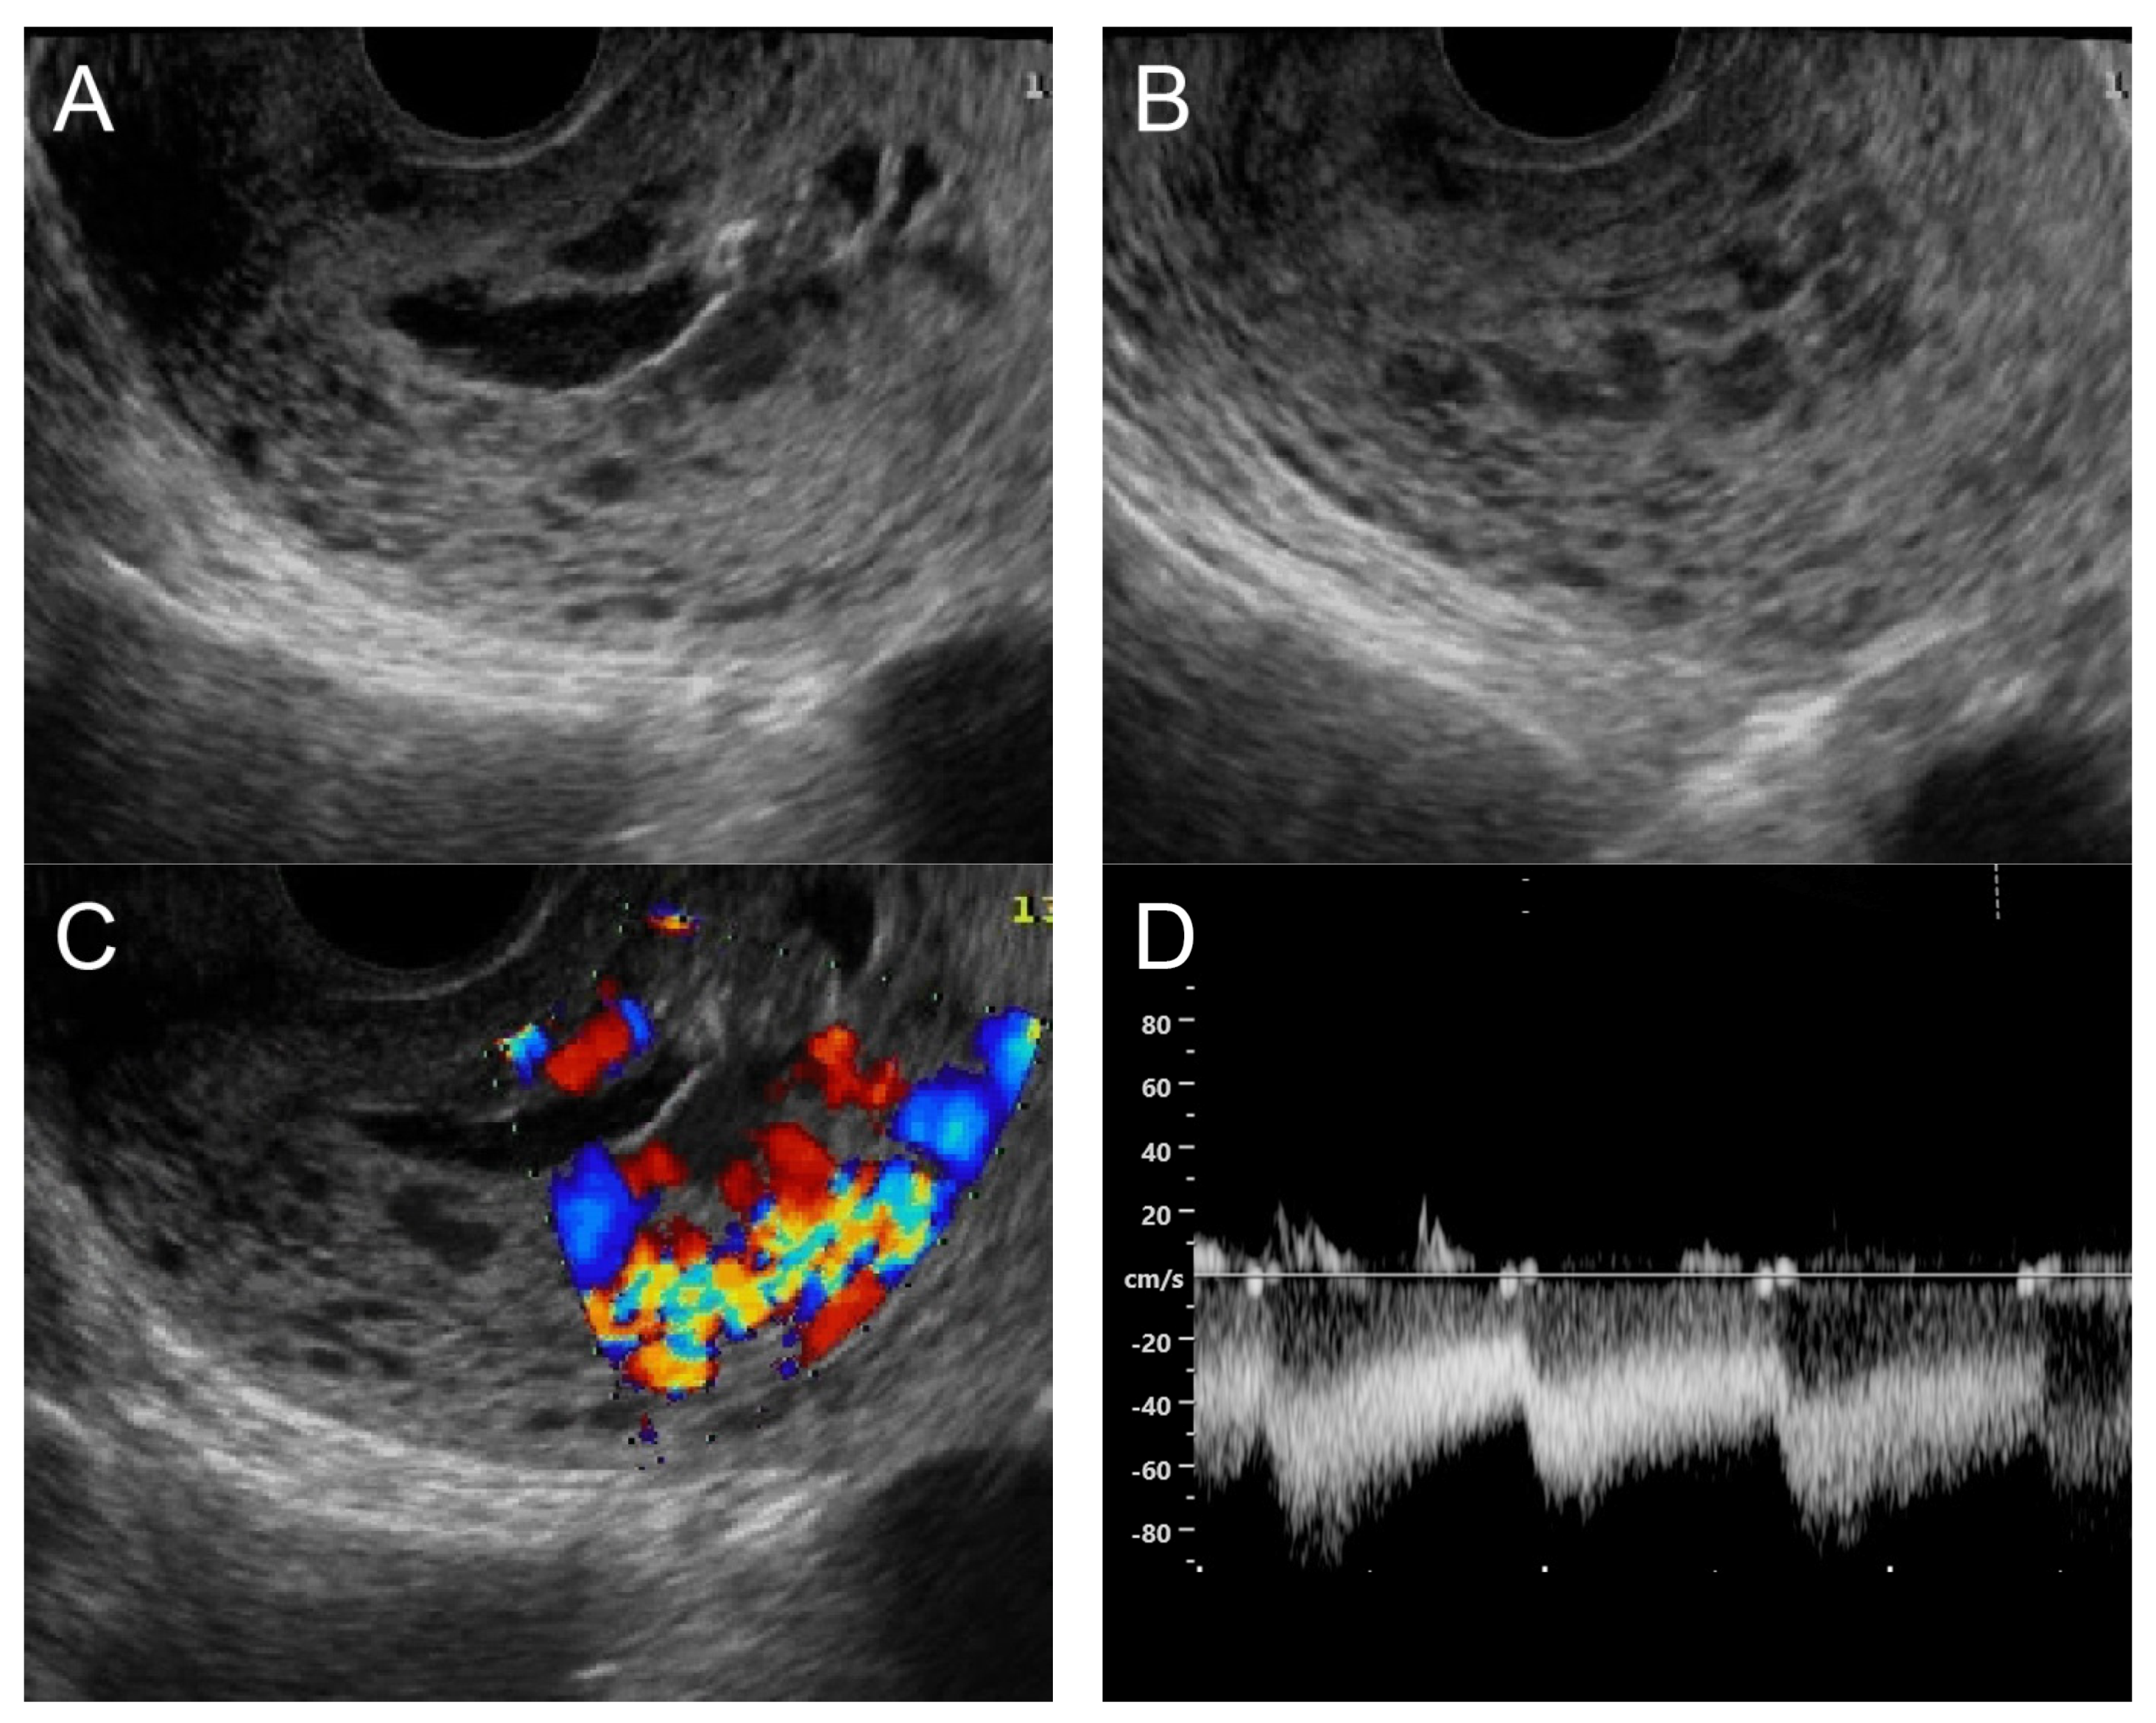

Figure 4. (A) Transvaginal ultrasound: sagittal scan of the uterus showed several dense small anechoic/hypoechoic tubular structures, mainly running to the endometrium, scattered throughout the anterior wall of the uterus; a thin endometrium; no other specific lesions of the uterus. There was anechoic fluid collection in the uterine cavity. (B) Cross-sectional scan of the fundus showed lesions with poorly defined outlines, containing several dense small anechoic/hypoechoic tubular structures, packed in the anterior wall. (C) Color flow mapping showed hyper-vascular areas in the myometrium, without well-defined lesion borders; multidirectional flow mainly localized at the anterior wall and the fundus. The main differential diagnosis was adenomyosis or gestational trophoblastic disease. (D) Spectral Doppler showed a high peak systolic velocity (~50 cm/s) with a low resistance index of 0.3. Note that in differentiating from adenomyosis, which sometime shows multiple minute anechoic or spongy-like areas but not lacunar lakes or tortuous vessels, adenomyosis is characterized by the absence of flow or minimal flow or by the presence of straight, scattered vessels traversing a hypertrophic myometrium [18,19], typically not containing a high flow peak systolic velocity, as seen in AMV, as mentioned earlier.